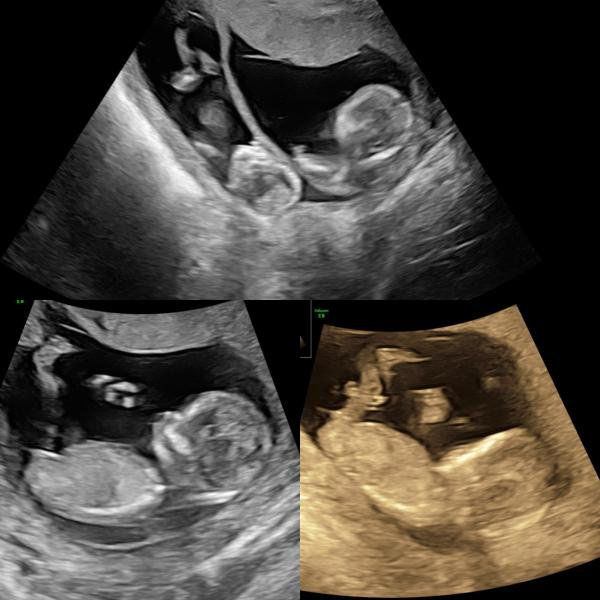

Graviditeten var ett faktum. 10/4 åkte vi ner till Gävle för första UL och läkaren hoppade nästan till lite när hon fick se två fina säckar med två små tickande hjärtan 🥰

Idag 12/6 var vi iväg på vårt andra ultraljud, på närmare ort. Även idag och inför var jag lite orolig att allt inte skulle se bra ut eftersom jag fortfarande inte haft några symptom alls.

Men där inne i magen dansade det omkring två pigga, helt perfekta små bebisar 🥰🥰🥰